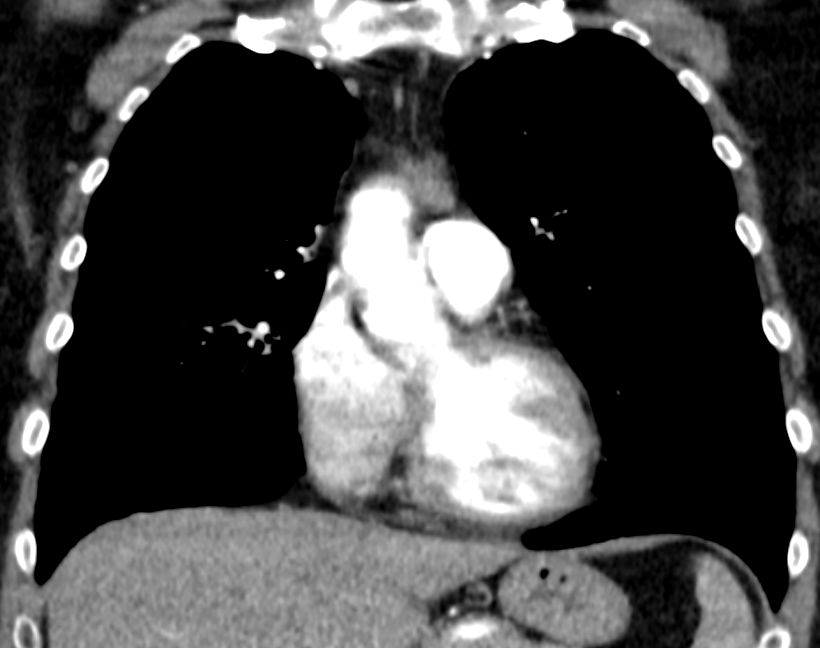

Diagnostik B3-Thymom mit Infiltration des Fettgewebes.